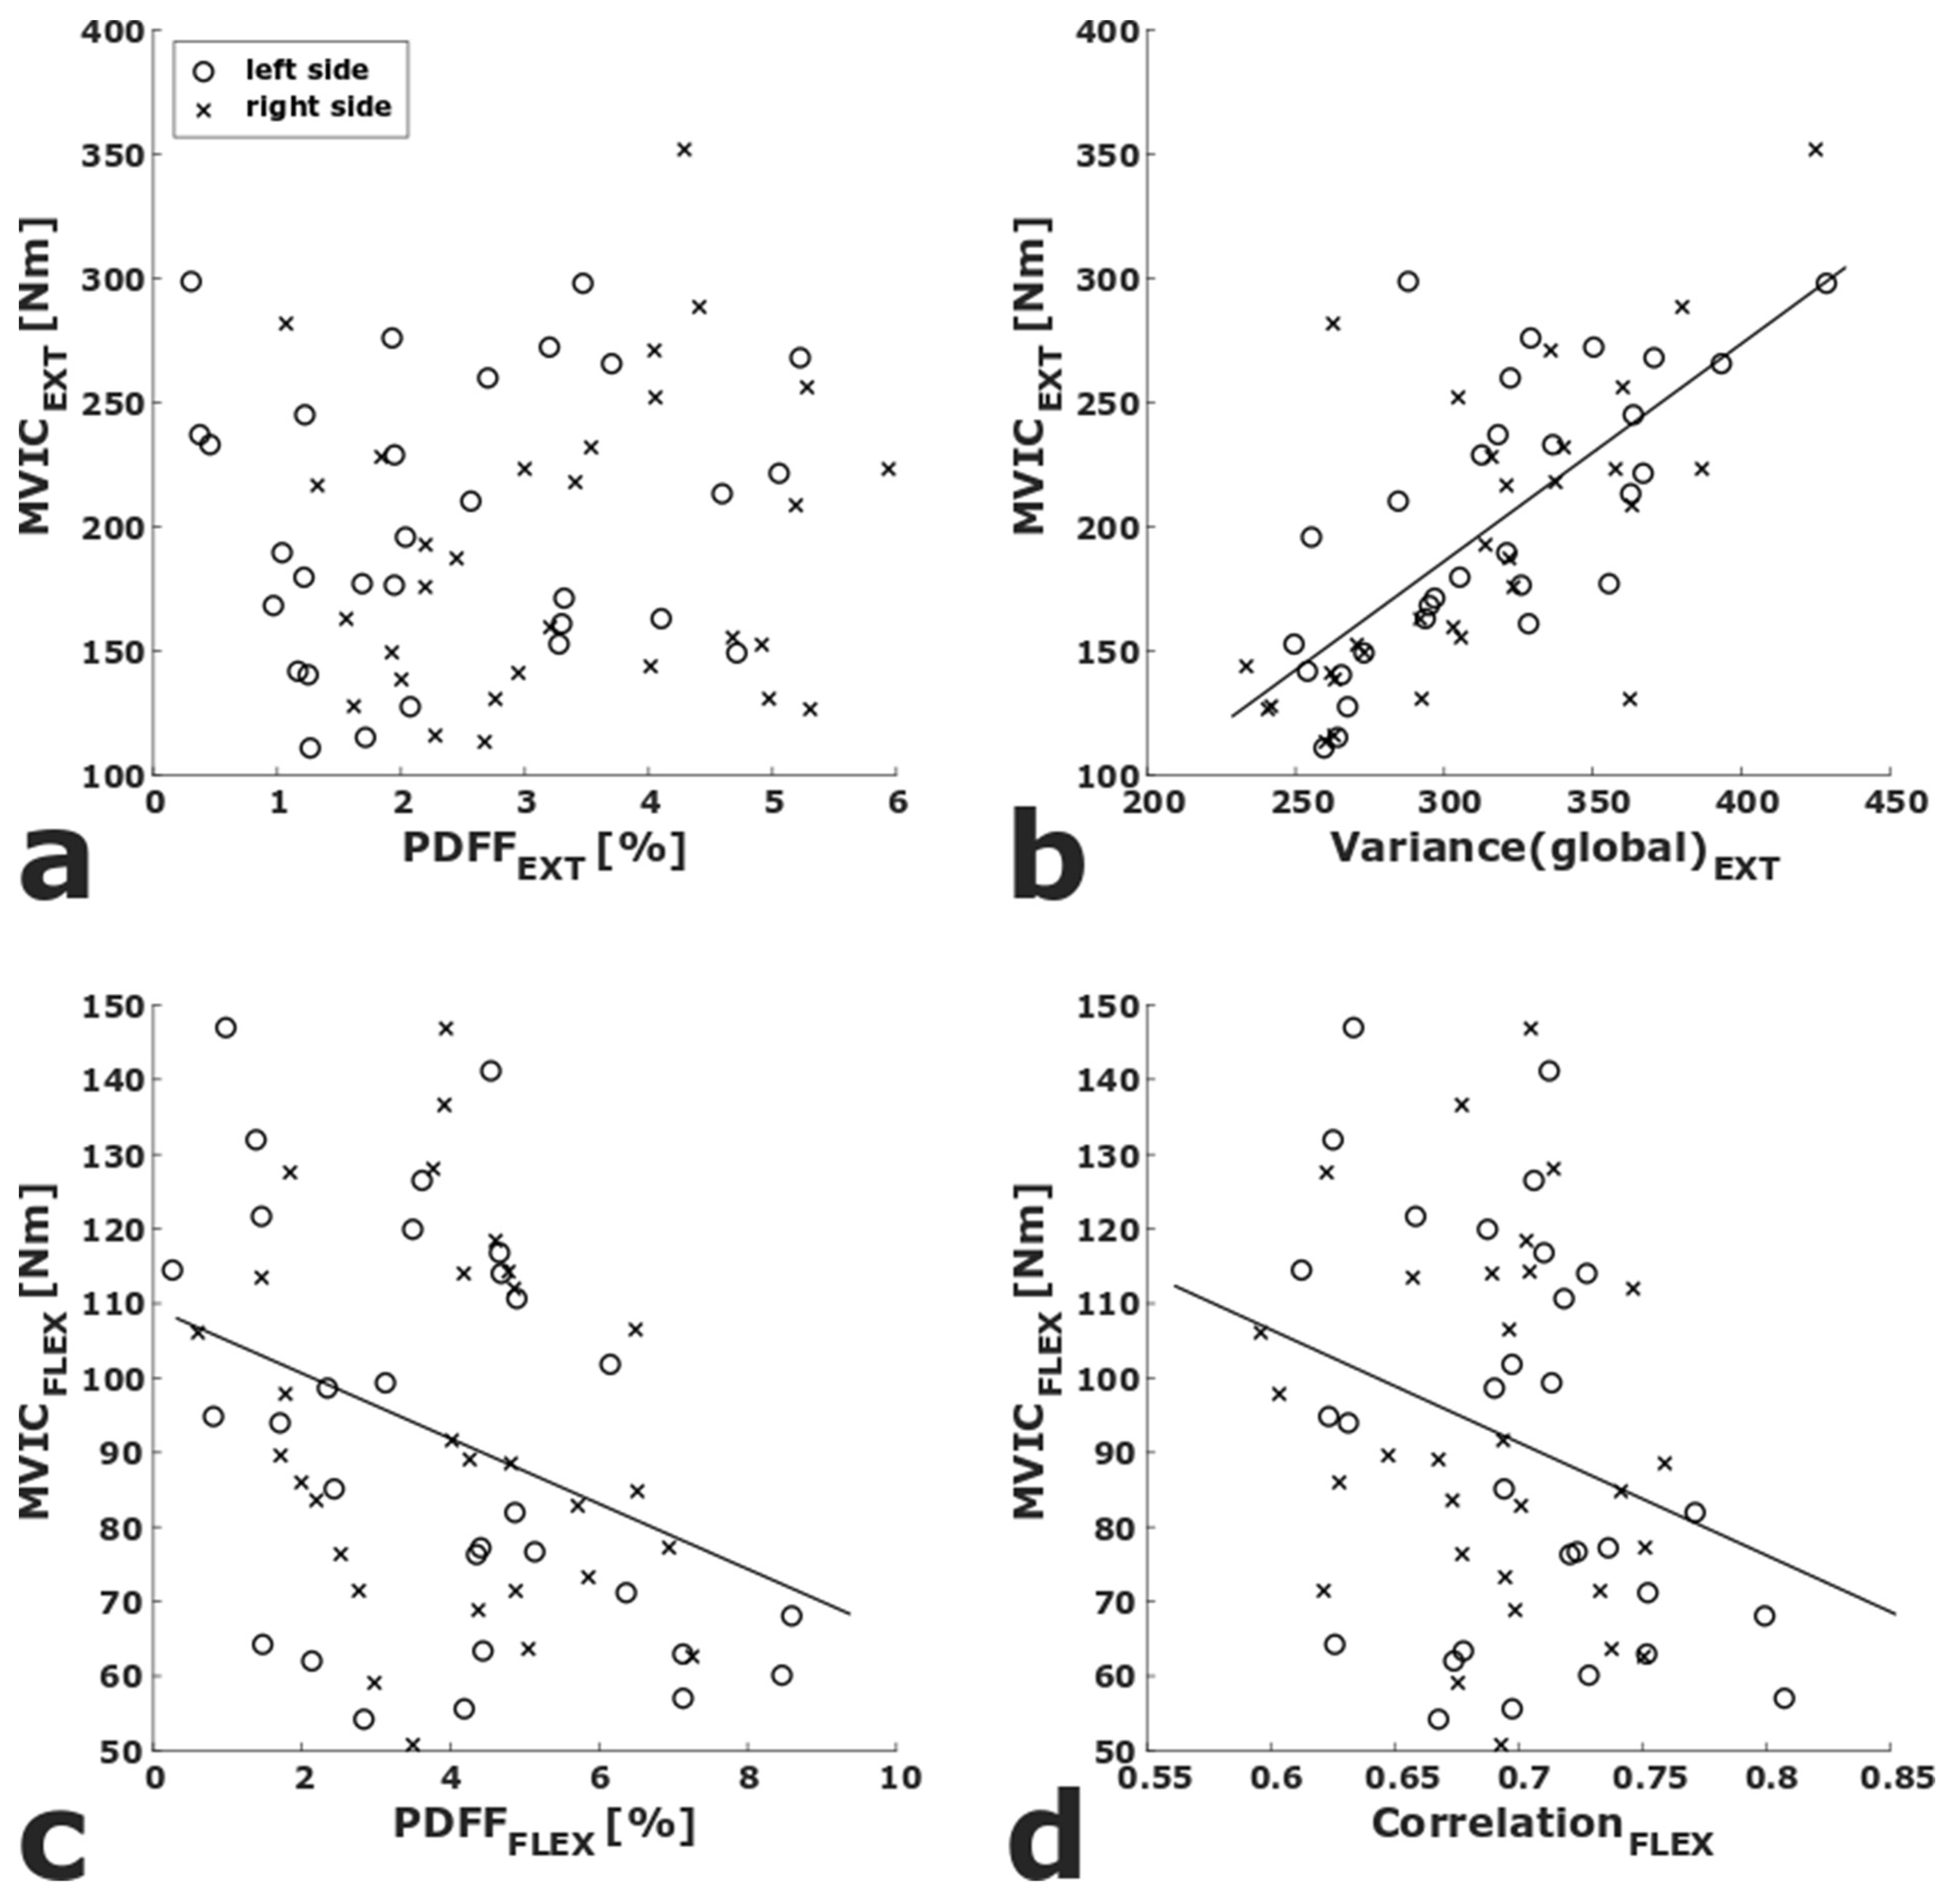

| Parameter | Extension | Flexion | ||

|---|---|---|---|---|

| R2adj | p | R2adj | p | |

| PDFF | 0.636 | 0.405 | 0.664 | 0.009 |

| Variance(global) | 0.712 | <0.001 * | 0.627 | 0.277 |

| Skewness(global) | 0.635 | 0.489 | 0.652 | 0.028 |

| Kurtosis(global) | 0.634 | 0.518 | 0.633 | 0.159 |

| Energy | 0.634 | 0.508 | 0.622 | 0.528 |

| Contrast | 0.649 | 0.103 | 0.623 | 0.432 |

| Entropy | 0.642 | 0.212 | 0.630 | 0.223 |

| Homogeneity | 0.640 | 0.264 | 0.630 | 0.214 |

| Correlation | 0.634 | 0.501 | 0.658 | 0.016 |

| SumAverage | 0.632 | 0.754 | 0.636 | 0.121 |

| Variance | 0.660 | 0.038 | 0.630 | 0.209 |

| Dissimilarity | 0.649 | 0.109 | 0.622 | 0.517 |